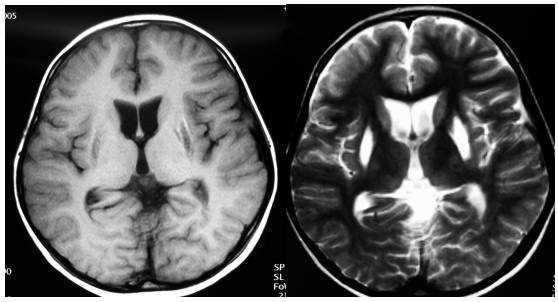

术后即清醒,拔除气管插管后回病房。当晚体温38.8℃,24h尿量4050ml。次日查血电解质:K+ 4.41mmol/L,Na+161mmol/L,Cl-122mmol/L。予口服弥凝片,0.025mg,一天两次,并予静脉补液对症处理。复查MRI示肿瘤基本全切(图2)

图2.术后复查MRI示肿瘤基本全切。